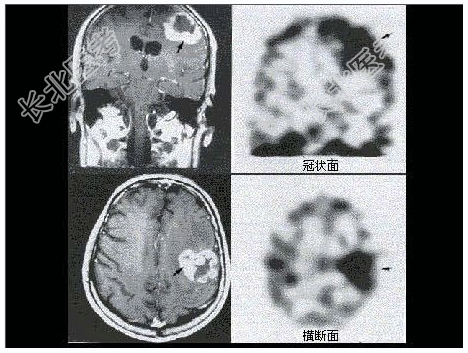

- [材料题] 男性患者恶性脑肿瘤术后6年复查,有放疗病史,无明显症状,行MRI及⁹⁹Tcᵐ-ECD脑血流灌注显像,后者提示局部脑血流减低,行Tl脑显像如图:

- 简答题1、可能的诊断是?

- 简答题2、T1脑显像在该案例中的作用是什么?如何解读其结果?